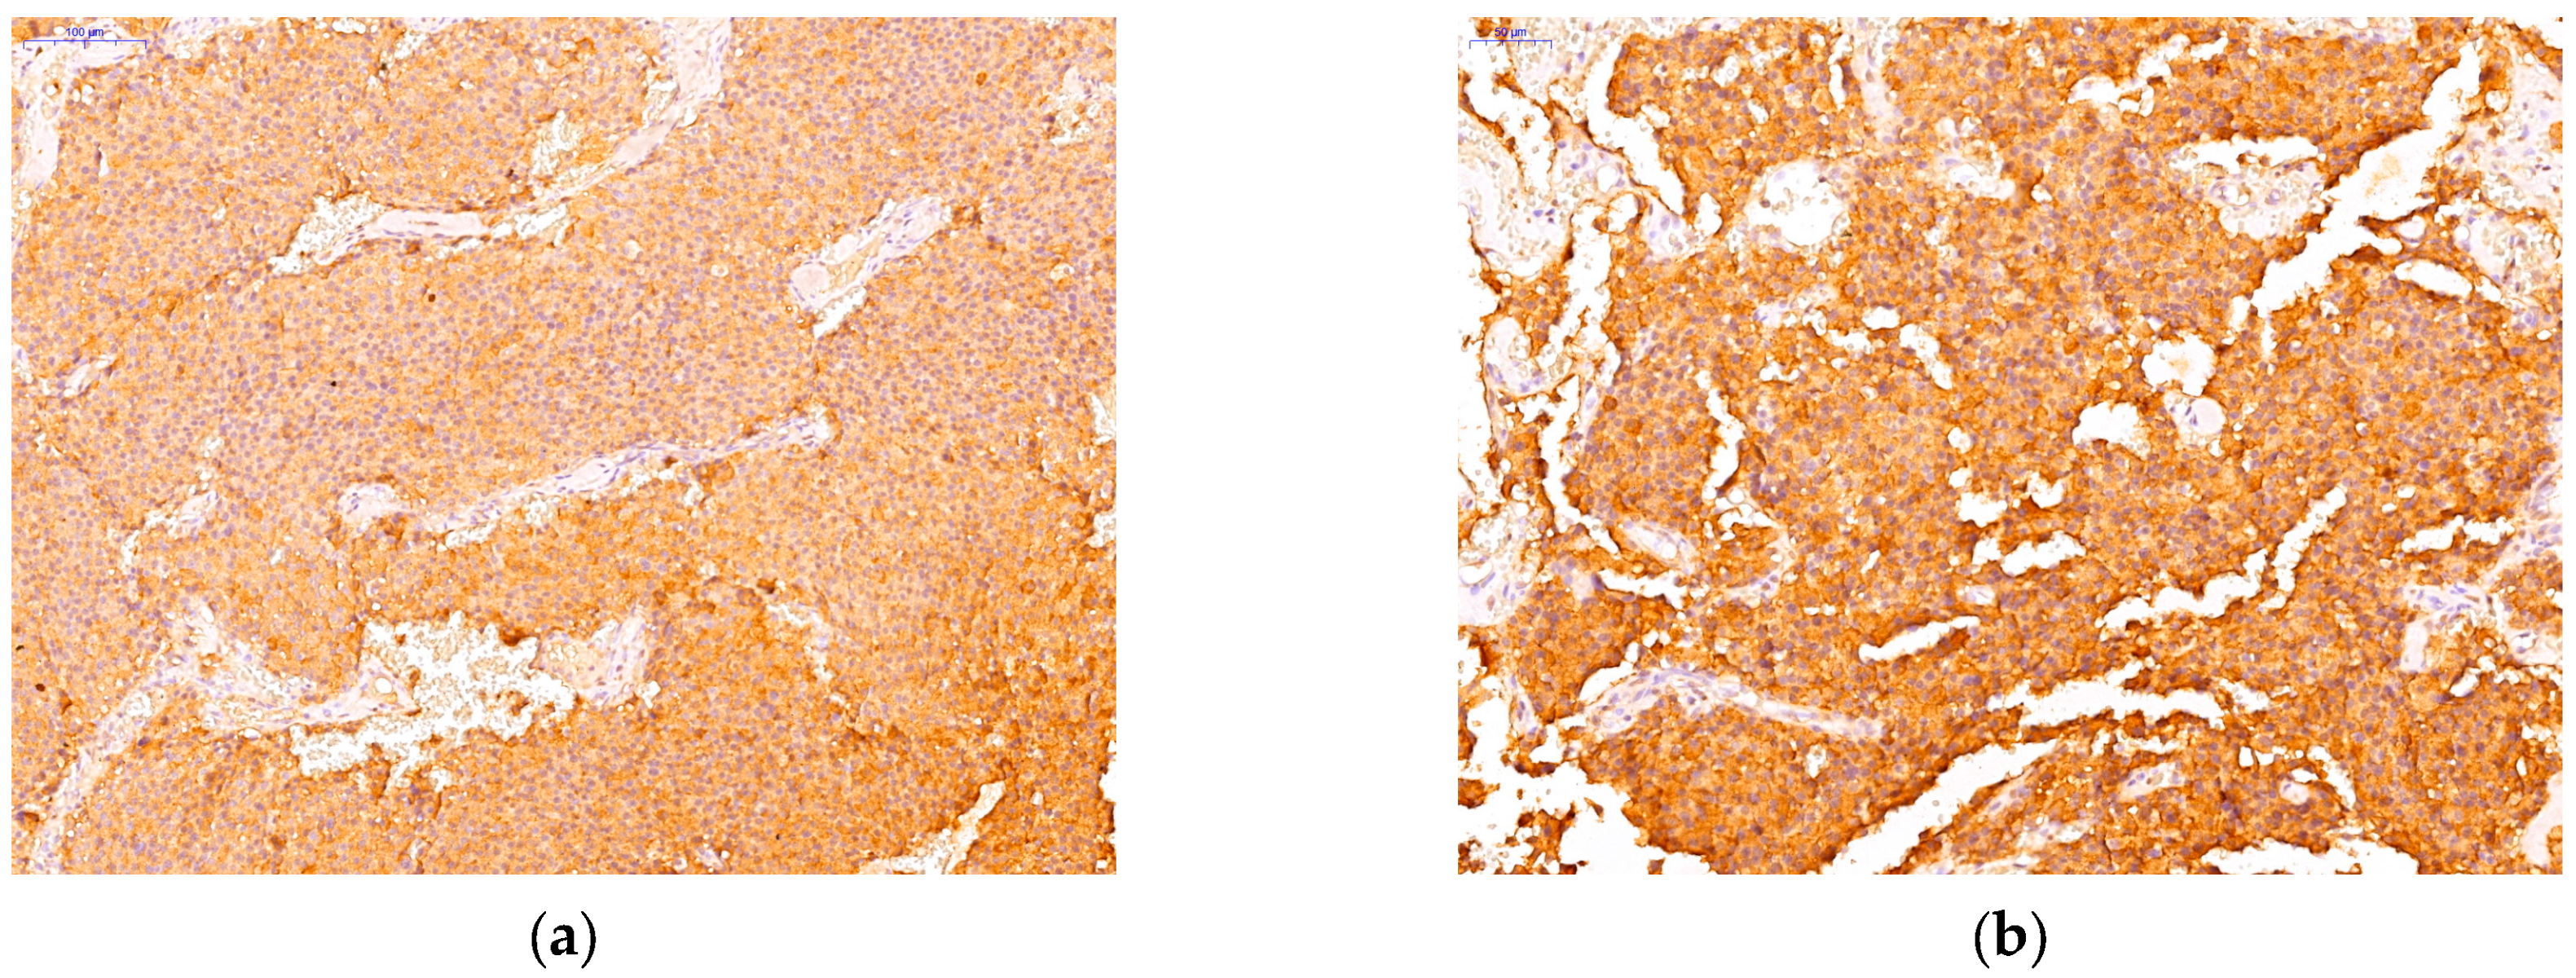

3.2. Immunohistochemichal Analysis